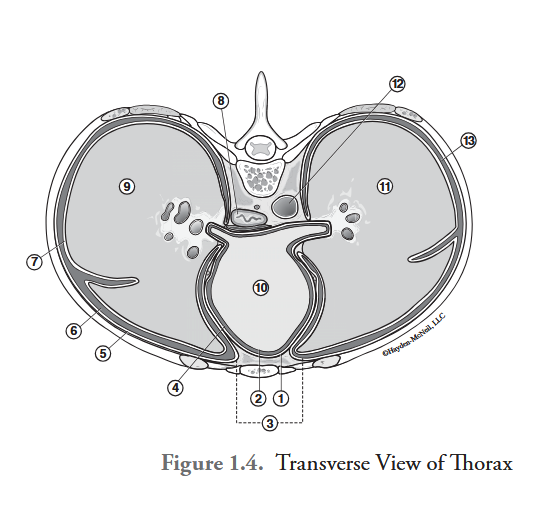

What is labeled #1?

parietal pericardium

What is labeled #2?

visceral pericardium (epicardium)

What is labeled #3?

mediastinum

What is labeled #4?

pericardial cavity

What is labeled #5?

parietal pleura

What is labeled #6?

right pleural cavity

What is labeled #7?

visceral pleura

What is labeled #8?

esophagus

What is labeled #9?

right lung

What is labeled #10?

heart

What is labeled #11?

left lung

What is labeled #12?

descending aorta

What is labeled #13?

left pleural cavity